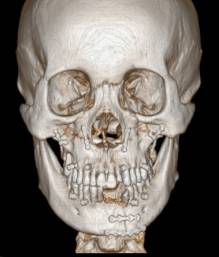

目前可使用软件将螺旋CT或锥束CT等影像学数据经计算机处理后,三维重建患者的颌骨形态,辅助牙颌面畸形的诊断,模拟手术截骨、移动、固定等,并制作相应的数字化导板辅助术中手术实施。同时因为计算机辅助手术设计可以更为直观的观察到术后颌骨的位置,更方便患者直观的了解手术效果,理解手术方案,便于医患沟通沟通。

(摘自“第四章第三节 牙颌面畸形治疗计划”)

计算机辅助正颌外科手术设计